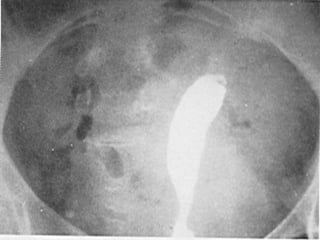

Congenital Uterine Anomaly n Diagnosis: History Pelvic exam Hysterosalpingography U/S MRI Laproscopy Hysteroscopy IVP or U/S (Exclude Renal anomaly )

Congenital Uterine Anomaly n Treatment: 1- Double uterus (didelphic uterus): no need to treat. 2- Bicornate ut. --------- Strassmann procedure ( if indicated ) 3- Ut. Septum --------- (BCP for dysmenorrhea ), Tompkins metroplasty or Hysteroscopic resection of septum ) 4- Unicornate ut. -------- Surgery indicated if there is blind horn which cause symptom----- surgical resection of blind horn.